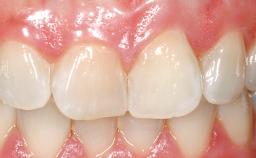

Late Placement of an Implant in a Maxillary Left Central Incisor Site

On examination, the patient had a low lip line and only displayed the coronal half of the anterior teeth when smiling.

A 36-year-old female patient was referred for the replacement of the upper left central incisor (tooth 21), which had fractured. Although the tooth had been asymptomatic for many years, the crown began to loosen, at which time she presented to her dentist for an assessment. Teeth 21 and 22 had both been endodontically treated many years previously. She was a healthy individual and a non-smoker.